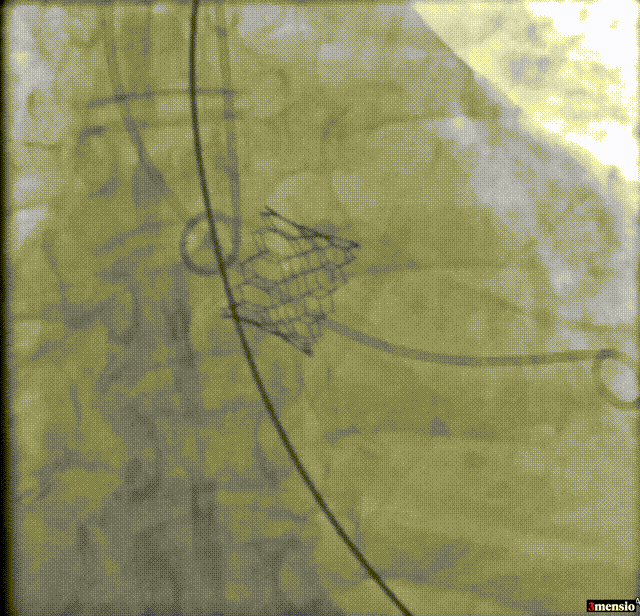

瓣膜释放

7.瓣膜释放后造影评估:未见明显反流,无瓣周漏,瓣膜形态和位置满意,双侧冠脉显影良好。瓣膜释放后流入/流出比例 = 100 : 0。瓣膜释放位置:90/10;

瓣膜释放后造影